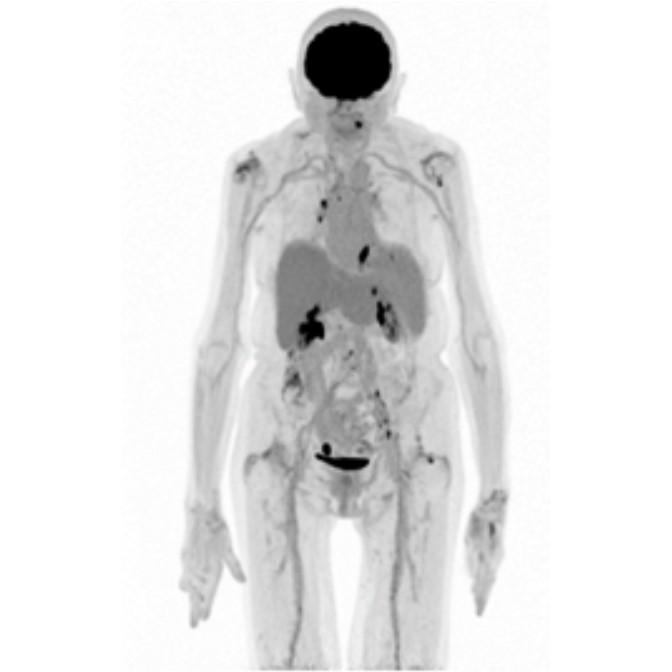

Partial nml and melanoma PET scan

The goal of PET/CT imaging in oncology is to enable the physician to distinguish between benign and malignant pathologies, to determine the extent of disease, to detect residual and recurrent tumors, to monitor the effectiveness of treatments, and to guide therapies.